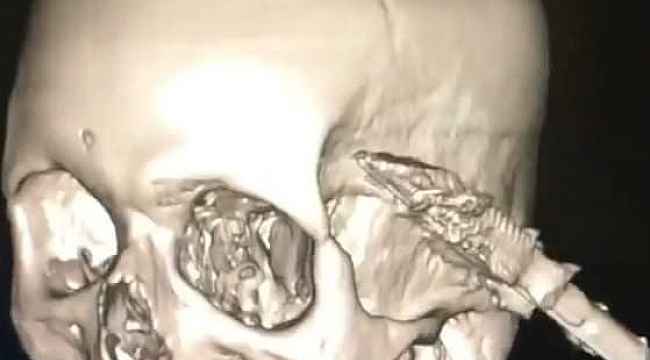

Kastamonu'da uyuduğu sırada koltuktan düşen yaşlı şahsın başına soba maşası saplandı. Maşanın bir kısmı itfaiye ekiplerince kesilirken, kalan kısım ise ameliyatla alındı.

Edinilen bilgiye göre, Araç ilçesinde ikamet eden ve ismi öğrenilemeyen yaşlı şahıs, koltukta uyuduğu sırada düşmesi sonucu kafasına soba maşası saplandı. İhbar üzerine yaralanan yaşlı şahıs, 112 Acil Sağlık ekiplerince Araç Devlet Hastanesine kaldırıldı. Burada ilk müdahalesi yapılan yaşlı şahıs, ardından Kastamonu Devlet Hastanesine sevk edildi. Burada tedavi altına alınan yaşlı şahsın kafasına saplanan soba maşasının bir kısmı, ilk olarak itfaiye ekiplerince kesildi. Ardından kafa tasında kalan kısım ise, yapılan ameliyat ile çıkarıldı. Kafasından soba maşası çıkarılan yaş şahıs, daha sonra servise alınarak tedavisine başlandı.

Edinilen bilgiye göre, Araç ilçesinde ikamet eden ve ismi öğrenilemeyen yaşlı şahıs, koltukta uyuduğu sırada düşmesi sonucu kafasına soba maşası saplandı. İhbar üzerine yaralanan yaşlı şahıs, 112 Acil Sağlık ekiplerince Araç Devlet Hastanesine kaldırıldı. Burada ilk müdahalesi yapılan yaşlı şahıs, ardından Kastamonu Devlet Hastanesine sevk edildi. Burada tedavi altına alınan yaşlı şahsın kafasına saplanan soba maşasının bir kısmı, ilk olarak itfaiye ekiplerince kesildi. Ardından kafa tasında kalan kısım ise, yapılan ameliyat ile çıkarıldı. Kafasından soba maşası çıkarılan yaş şahıs, daha sonra servise alınarak tedavisine başlandı.